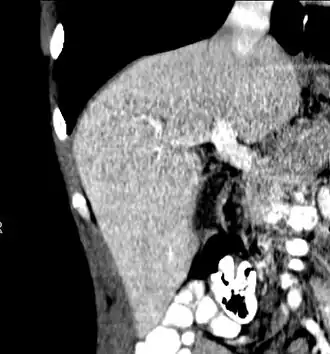

CT scan showing an adult liver in the axial plane

Organogenesis, the development of the organs, takes place from the third to the eighth week during embryonic development. The origins of the liver lie in both the ventral portion of the foregut endoderm (endoderm being one of the three embryonic germ layers) and the constituents of the adjacent septum transversum mesenchyme. In the human embryo, the hepatic diverticulum is the tube of endoderm that extends out from the foregut into the surrounding mesenchyme. The mesenchyme of septum transversum induces this endoderm to proliferate, to branch, and to form the glandular epithelium of the liver. A portion of the hepatic diverticulum (that region closest to the digestive tube) continues to function as the drainage duct of the liver, and a branch from this duct produces the gallbladder.[37] Besides signals from the septum transversum mesenchyme, fibroblast growth factor from the developing heart also contributes to hepatic competence, along with retinoic acid emanating from the lateral plate mesoderm. The hepatic endodermal cells undergo a morphological transition from columnar to pseudostratified resulting in thickening into the early liver bud. Their expansion forms a population of the bipotential hepatoblasts.[38] Hepatic stellate cells are derived from mesenchyme.[39]